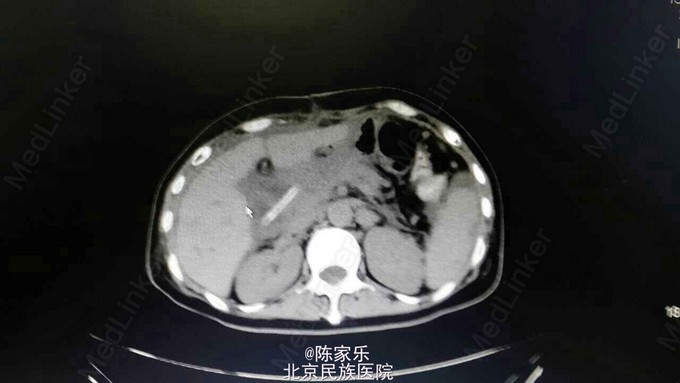

主诉:上腹部疼痛伴呕血2小时 现病史:女,55岁,2小时前无明显诱因突发上腹部疼痛,疼痛无向他处放射,伴恶心、呕暗红色血,量血100ml,无腹胀、腹泻、头晕、心季等不适。 既往史:1个月前因胰头癌行胰十二指肠切除术。否认高血压、糖尿病、肝炎、胃溃疡病史。

查体:腹部平软,上腹部轻压痛,无肌紧张、反跳痛。 实验室检查:未见明显异常 CT:胰十二指肠切除术后改变,肝门区及肝周积液,肝右叶近包膜区低密度灶,肝内胆管轻度扩张。

术前诊断:上消化道出血,胰十二指肠切除术后 保守治疗过程中再次出现消化道出血。随行剖腹探查术,术中腹腔粘连严重,肝脏与肠管粘连严重,无法辨别组织关系,未见明确出血点和积血,沿肝脏下缘分离粘连肠管及网膜组织,仔细辨别胆肠吻合口,考虑吻合口周围血管瘤破裂出血,动脉瘤直接破裂入肠腔。 术中诊断:胆肠吻合口假性动脉瘤破裂出血。